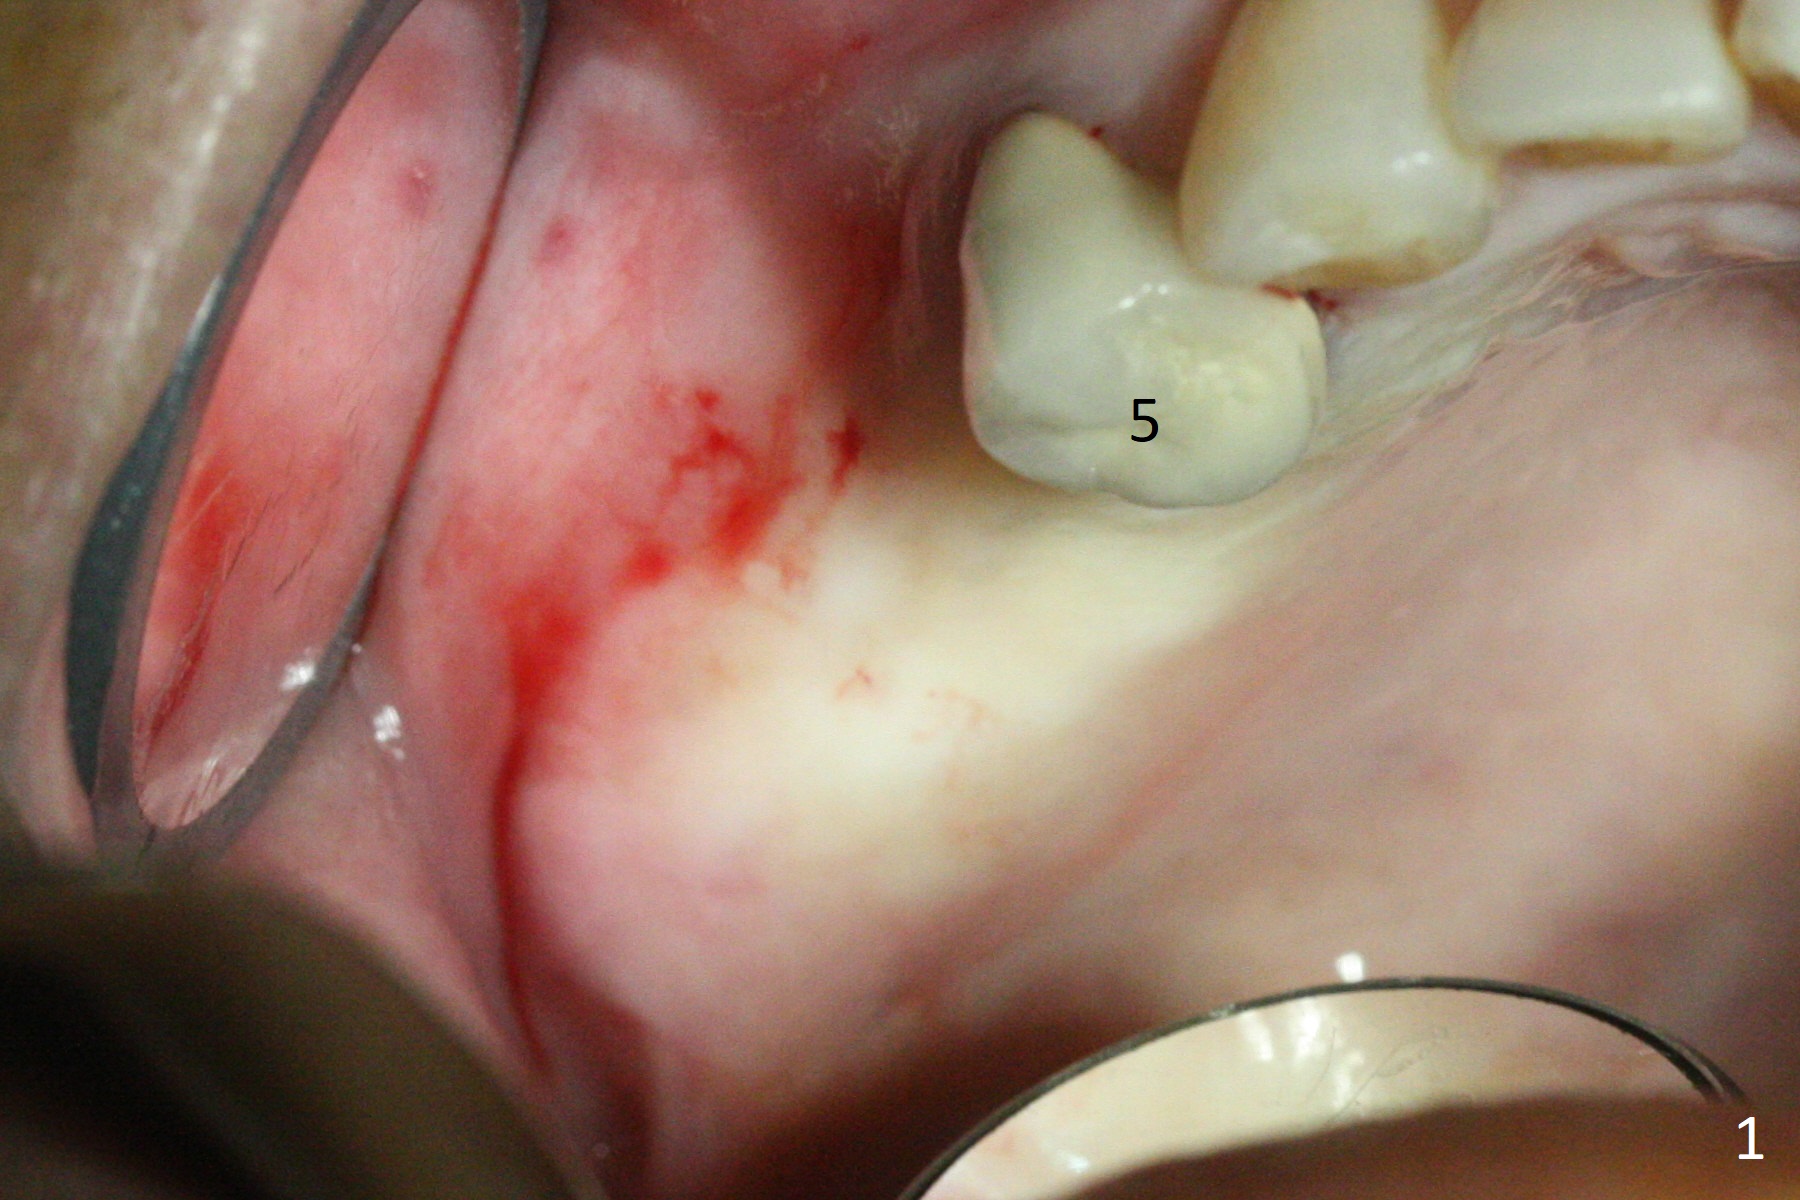

The ridge at #3,4 is wide (Fig.1). A surgical stent is placed (Fig.2) for initial osteotomy (Fig.3). When the stent is removed, the osteotomies need to move palatal (Fig.4 arrows). As two of 1.2 mm drills are in place (Fig.5), mesiodistal trajectories are found off (Fig.6). After the trajectories are corrected (Fig.7), the depth cannot be determined with PA (Fig.8, as compared to Pan (Fig.9)). Following 4.3 and 3.2 mm final drills at #3 and 4, 4.5x13 and 3.8x15 mm implants are placed with insertion torque of 35 and 50 Ncm, followed by 5.5x4(3) and 4.5x4(2) mm abutments (Fig.10). BWs show incomplete placement of the implant at #4 distal (Fig.11,12). Later the implant is placed ~ .5 mm deeper. Periodontal dressing is applied postop. CT-assisted surgical guide must be more efficient for this case with wide ridge. There is no bone loss around the implants 3 moths postop